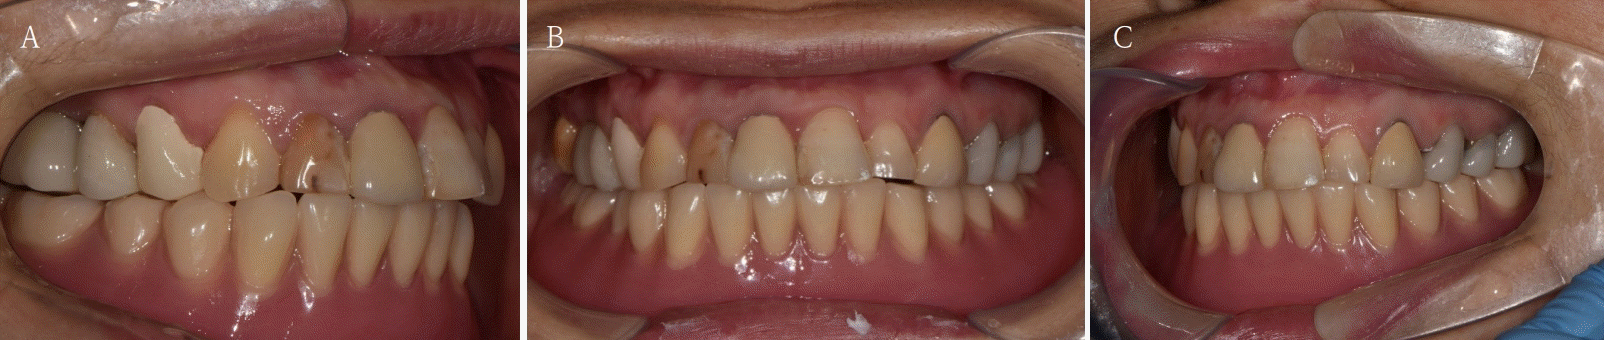

Fig. 5.

The patient is satisfied with the occlusion and vertical dimension of newly fabricated temporary denture. A. Right side view. B. Frontal view. C. Left side view.

본 증례는 44세 여환으로, 하악 의치가 계속 탈락하여 재제작을 원한다는 주소로 내원하였다. 상악은 고정성 수복물, 그리고 하악은 총의치를 착용 중이었고 하악 양측 구치부의 심한 골 흡수로 인해 유지력 소실로 불편감을 호소하였다. 3개월 전 하악 양측 견치를 발거한 이후로 하악 국소의치를 총의치로 전환하였고, 총의치는 구치부의 심한 교합면 마모와 의치의 후방부가 후구치 삼각 융기를 피개하지 않는 형태였다. 전신 병력으로는 지적장애 및 골관절염으로 약 2개월 간 약물 복용 중이었다. 상악 우측 제1대구치와 제2대구치, 제1소구치 그리고 제2소구치는 우식이 진행된 상태였고, 우측 제2소구치와 우측 제1대구치는 근관치료가 완료된 후 수복되지 않은 상태였다. 상악 좌측 제1소구치와 제2소구치, 그리고 제1대구치 수복물 하방으로 이차 우식이 진행된 상태였고, 전체적으로 교합평면이 균일하지 않은 형태였다(Figs. 1-3).상악 우측 구치부의 수복되지 않은 치아와 상악 좌측 보철물 하방의 이차 우식이 있는 치아는 모두 우식 제거가 필요하여 양측 구치부 각각 3개의 치아는 재수복을 결정하였고, 하악은 구치부의 심한 치조골 흡수로 인해 의치 사용은 불가할 것으로 판단하여 전방부에 임플란트를 식립하여 구치부는 캔틸레버 형태를 가지는 all-on-X 수복을 계획하였다. 의치의 수직고경에 맞춰 교합 평면을 균일하도록 하여 왁스업 시행하였고(Fig. 4), 이후 적절한 교합 수직 고경의 임시 의치를 제작하였다. 약 2개월의 적응기간을 거쳐 의치 적응도와 수직 교합 고경을 평가하였고 적절한 기능과 심미를 확인하였다. 상악 우측 제1소구치와 제2소구치, 제1대구치 그리고 상악 좌측 제1소구치와 제2소구치, 제1대구치는 우식을 제거한 다음, 임시 보철물로 재수복하여 적절한 교합 평면을 설정하였다(Fig. 5).환자가 적응한 임시 의치를 모델 스캔(Medit T710, Medit, Seoul, Korea)하여 프린팅용 레진(Graphy Tera Harz SG-100, Graphy, Seoul, Korea)을 이용하여 3D 프린팅하였고, 출력된 의치에 방사선 불투과성 레진(G-æenial Universal Flo, GC, Luzern, Swiss)을 부착하여 레진 마커를 형성하였다. 레진 마커를 부착한 프린팅 의치를 장착한 채로 콘빔 전산화 단층촬영(CBCT, R2 Studio Q, Megagen, Seoul, Korea)를 촬영하였다(Fig. 6). 촬영한 CBCT 데이터와 의치 스캔 파일을 중첩하여 CAD 소프트웨어(R2 Studio Q, Megagen, Seoul)를 통해 이상적인 임플란트 식립을 계획하였다. 전후방 거리를 연장하여 적절한 캔틸레버를 부여하기 위해 전방부에 3개의 임플란트를 식립하고, 양측 후방부에는 약 30도 경사진 임플란트를 식립하도록 계획하였다(Fig. 7).가이드는 상악의 자연 치열과 대합되는 의치 복제 형태의 상부 가이드, 그리고 가이드 핀이 존재하는 하부 가이드로 이루어지도록 디자인되었다(Fig. 8). 상부 가이드는 임시 의치의 스캔 데이터를 이용해 상부 가이드의 하부면과 하부 가이드의 상부면이 장착되어 구내에서 적합될 수 있도록 CAD 소프트웨어(Meshmixer, Autodesk, San Francisco, CA, USA) 상에서 디자인되었다. 임시 의치의 하부면과 하부가이드의 하부면을 치은과 중첩시켜 어버트먼트의 위치에 홀을 형성한 다음 3D 프린팅(Graphy Tera Harz SG-100, Graphy, Seoul, Korea) 하였다. 수술 당일 장착될 임시 보철물 또한 동일한 CAD 소프트웨어를 통해 제작하였다.수술 당일 이중 가이드를 구내에 장착하여 하부가이드를 고정 핀으로 고정시킨 후(Fig. 9), 계획된 위치에 임플란트 고정체를 식립하였다. 임플란트는 5개 모두 외부 연결형 고정체(AnyOne External, Megagen, Seoul, Korea)를 사용하였고, 식립 시 식립 토크는 모두 40N 이상, ISQ는 70이상으로 양호한 초기 고정력을 확보하였다(Fig. 10). 즉시 부하를 위해 기성 어버트먼트를 체결하였고, 임시 보철물을 장착하여 양측 소구치부에서의 균일한 교합을 확인하였다(Fig. 11).임플란트 주위 골과 치은의 회복을 위해 약 2달간 임시 보철물을 경과 관찰하였고, 이후 최종 보철을 위한 인상 채득을 시행하였다. 상하악 임시 보철물을 장착한 중심교합 상태에서 구내 스캔(Trios 4, 3 Shape, Copenhagen, Denmark)을 시행하여 악간 관계를 채득하였다(Fig. 12). 임시 보철물을 제거한 상태에서 하악의 전방부 3개의 임플란트에 scan body(Scan Abutment, Megagen, Seoul, Korea)를 연결하고, 양측 최후방 임플란트 2개에는 각각 Ti base multi-unit abutment(multi-angled abutment, Osstem, Seoul, South of Korea)를 30Ncm으로 체결한 후 multi scan body(TS Multi scanbody, Osstem, Seoul, Korea)를 연결하여 구내 스캔(Trios 4, 3Shape, Copenhagen, Denmark)을 시행하였다. 이후 스캔 바디를 연결하여 채득한 스캔 파일을 상하악 임시 보철물 상태에서 채득한 스캔 파일과 중첩하여 CAD 소프트웨어(exocad GmbH, Darmstadt, Germany)에서 최종 보철물을 디자인하였다(Fig. 13).최종 보철물은 양측 최후방 임플란트 고정체에 각각 Ti-base(TS multi Ti base, Osstem, Seoul, Korea)와 접착된 나사 유지형 단일 지르코니아 크라운으로, 지르코니아 블록(Zircen, Kuwotech, Gwangju, Korea)을 밀링하여 제작하였고, 치경부 하방으로 포세린으로 치은 형태를 부여하였다. 전방부 3개의 임플란트 고정체에는 맞춤형 지대주를 제작하여 30N으로 체결하였고, 양측 최후방 고정체는 20Ncm으로 체결한 후 레진 시멘트(Rely X U200; 3M ESPE, St. Paul, MN, USA)로 접착 시행하였다. 장착 후 중심교합시 양측의 제1대구치 부위에서 교합력이 적게 가해지도록 교합 조정 시행하였으며, 전방과 측방운동시에 임플란트 상호보호교합이 되도록 조정하였다. 또한 연결부 하방으로 치실을 통과시켜 치은 점막 사이 공간을 평가하였으며, 구강 위생 관리의 용이성을 확인하였다. 이후 1주, 1개월, 3개월 경과 관찰하였고, 환자는 저작이나 심미, 발음 등에서 만족해하였다(Figs. 14 and 15).